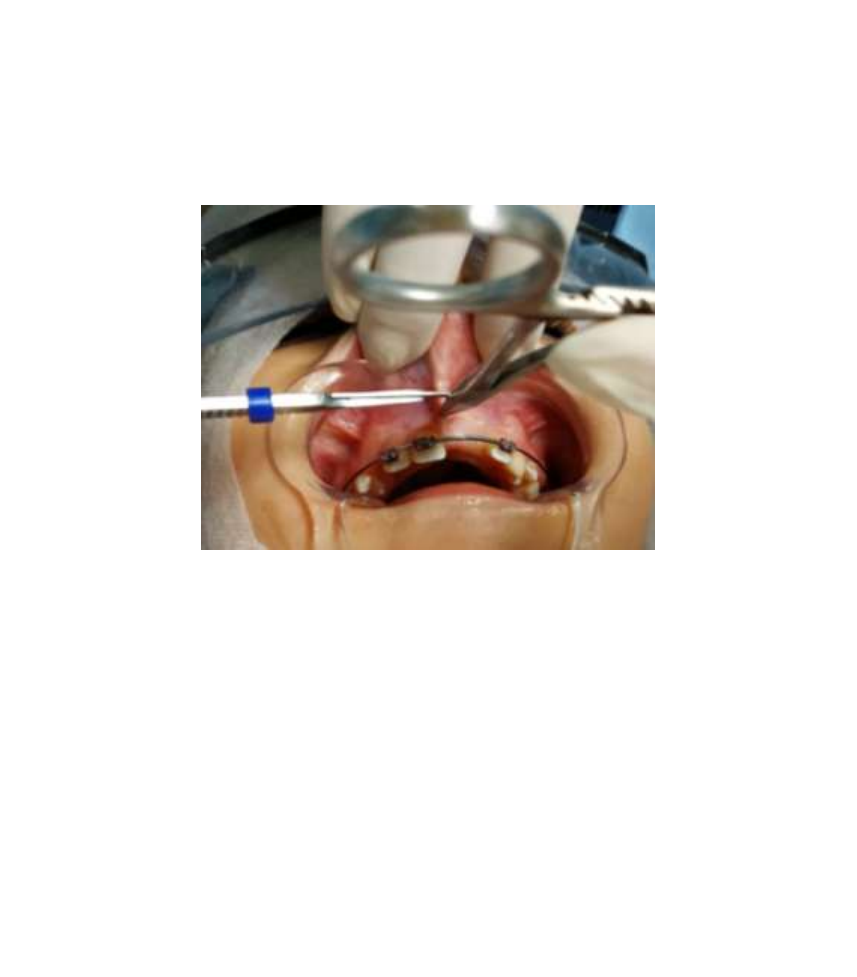

freio labialfreio superiorfreio emfreio bebefreio Freiofreio lingual:freio TUDOfreio ofreio quefreio vocêfreio precisafreio saberfreio sobrefreio ofreio assunto!freio FRENECTOMIAfreio Grátis:freio FREIOS